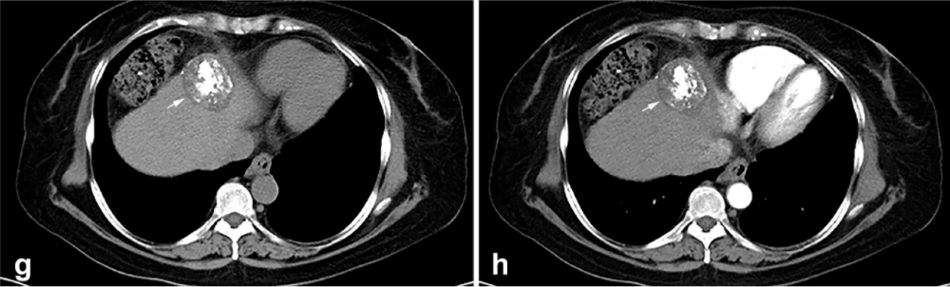

背景:由于一些原因,位于膈肌附近的腫瘤的熱消融在技術(shù)上具有挑戰(zhàn)性。首先,術(shù)中計(jì)算機(jī)掃描和超聲檢查無(wú)法清晰顯示射頻消融/微波消融切緣。第二,消融過程中不利的針分布和過熱可能導(dǎo)致肝包膜破裂,并對(duì)膈、肺和心臟造成嚴(yán)重?fù)p傷。第三,即使使用人工腹水,仍有9~22%的患者因肝周粘連或腫瘤位置靠近肝表面而導(dǎo)致膈肌熱損傷。冷凍消融可能是毗鄰膈肌的HCC的一種有前途的治療方法,因?yàn)樵谙谶^程中使用CT和US可以很好地顯示腫瘤邊緣。盡管一些研究評(píng)估了在高危區(qū)域使用冷凍消融治療HCC,但很少有研究針對(duì)膈肌臨近區(qū)域。

背景:肝癌是中國(guó)最常見的惡性腫瘤之一,發(fā)病率和死亡率都很高。雖然手術(shù)切除是最好的治療方法,但大多數(shù)患者處于晚期或直到住院才有手術(shù)指征。對(duì)于單個(gè)腫瘤直徑小于5厘米的患者,微創(chuàng)治療與手術(shù)切除效果相當(dāng);多個(gè)病灶小于3個(gè),單個(gè)病灶最大直徑小于3cm;不侵犯血管、膽管、鄰近器官和遠(yuǎn)處轉(zhuǎn)移。雖然一些傳統(tǒng)消融技術(shù)方式可以使部分患者受益,但不適用于特殊部位肝癌(定義為毗鄰大血管、肝外臟器和重要結(jié)構(gòu)的腫瘤)的治療。冷凍消融作為一種相對(duì)較新的治療方式,具有明顯的冰球效果、療效好、激活抗腫瘤免疫、并發(fā)癥發(fā)生率低等優(yōu)點(diǎn),尤其適用于特殊部位肝癌患者的治療。我們的研究目的是探討CA治療特殊部位肝癌的安全性、可行性和有效性。

① 在我們的研究中,技術(shù)成功率為100%。動(dòng)態(tài)增強(qiáng)MR檢查隨訪1個(gè)月,66例患者首次技術(shù)有效率為65例(98.5%),MR影像學(xué)未發(fā)現(xiàn)外周臟器損傷。中位隨訪時(shí)間14個(gè)月(范圍2-28個(gè)月)。高危部位肝癌局部腫瘤進(jìn)展率曲線:6、9、15和24個(gè)月的累積局部腫瘤進(jìn)展率分別為10.2%、16.5%、20.9%和30.5%。